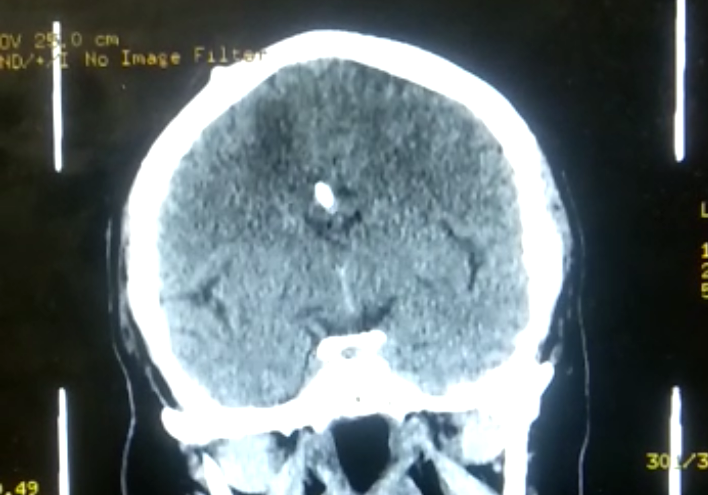

Figure 2 Sagittal image of the brain to show surgery and edema, taken on March 30.